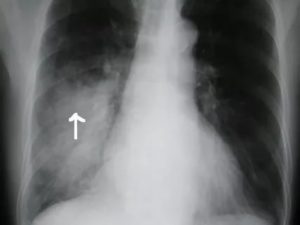

- Крупозная пневмония. Наблюдаются изменения нормального легочного рисунка, жидкость в полости плевры, признаки инфильтрации одной из долей легкого, расширение корней. По мере развития воспалительного процесса выраженность изменений и интенсивность окраски затемнений усиливается.

Крупозный или долевой вид пневмонии характеризуется большими потемнениями средней интенсивности, поражающими одну или обе доли лёгких.

Выделяют следующие признаки, видимые при расшифровке снимков:

- тени на одной или двух сторонах;

- смещение пространства среднего отдела грудной клетки к области воспаления;

- сильная деформация рисунка лёгких;

- заполнение лёгочного пространства жидкостью;

- изменение куполов диафрагмы;

- расширенные корни лёгких.

Для точной диагностики крупозного воспаления проводят прямую и боковую рентгенографию для оценки тяжести поражения лёгочных долей.

Сравнение здоровых и воспаленных легких на рентгенографии Абсцесс лёгких на рентгеновском снимке Абсцесс при левостороннем верхнедолевом воспалении лёгких Очаговая пневмония Крупозная пневмония на рентгене Казеозная пневмония